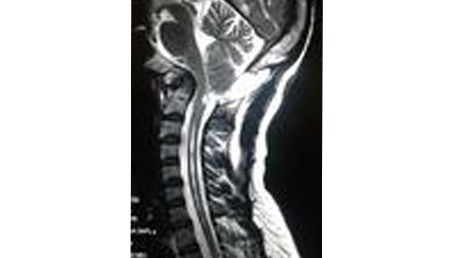

2. Arnold chiari malformation with syrinx.